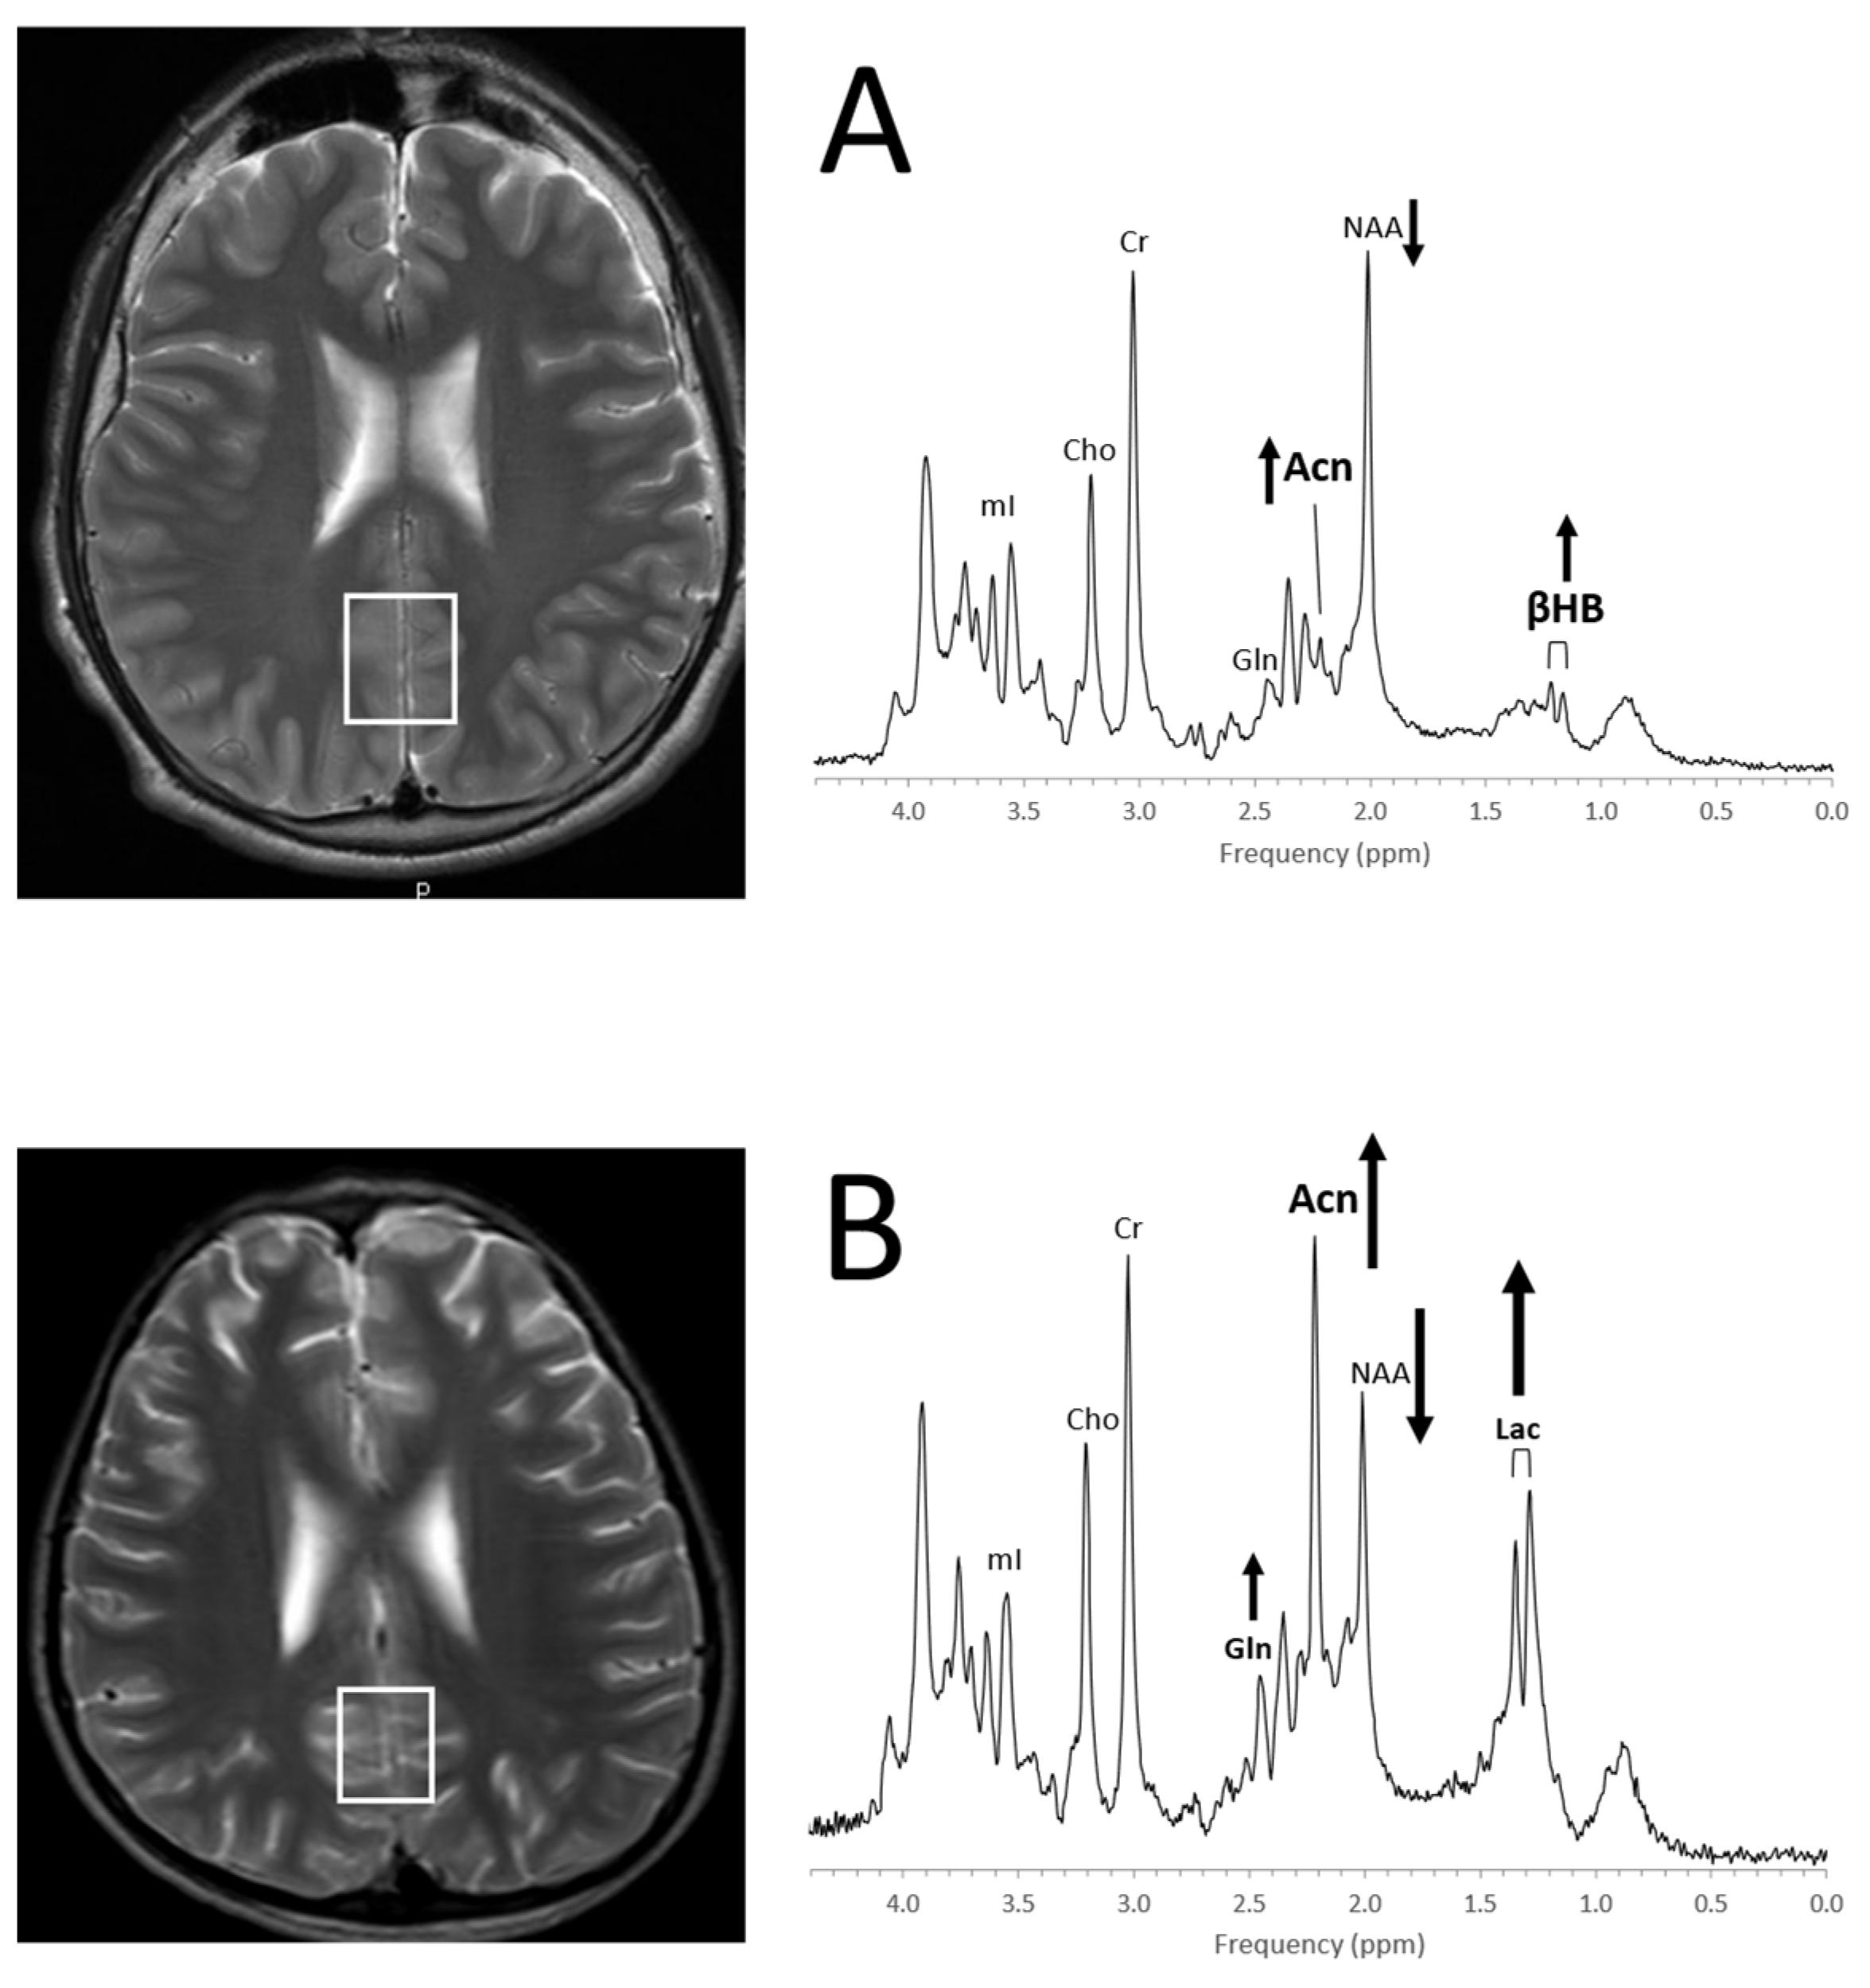

From www.mdpi.com

Diagnostics Free FullText Proton MR Spectroscopy of Pediatric Brain Disorders What Is Spectroscopy In Mri Mr spectroscopic imaging (mrsi) has become a valuable tool for quantifying metabolic abnormalities in human brain, prostate, breast. Spectroscopy is a series of tests that are added to the mri scan of your brain or spine to measure the chemical metabolism of a suspected tumor. Learn what magnetic resonance spectroscopy (mrs) is and how it differs from an mri to. What Is Spectroscopy In Mri.

From www.researchgate.net

1 HMR spectroscopy of medulloblastoma. 1 H spectra Download Scientific Diagram What Is Spectroscopy In Mri Learn what magnetic resonance spectroscopy (mrs) is and how it differs from an mri to help diagnose cancerous tumors and other diseases. Magnetic resonance spectroscopy (mrs) is a technique which can provide information on tissue chemistry non. Mr spectroscopic imaging (mrsi) has become a valuable tool for quantifying metabolic abnormalities in human brain, prostate, breast. What is an mri spectroscopy. What Is Spectroscopy In Mri.